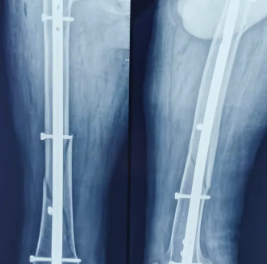

切开复位内固定术

通过植入金属器械(如螺钉、钢板、髓内针等)直接固定骨折断端或骨骼。

(图片来源:网络)

- 适用情况:关节内骨折、难以维持复位的复杂骨折、骨不连等情形。

- 局限性:植入物可能会引起骨质疏松、感染风险。